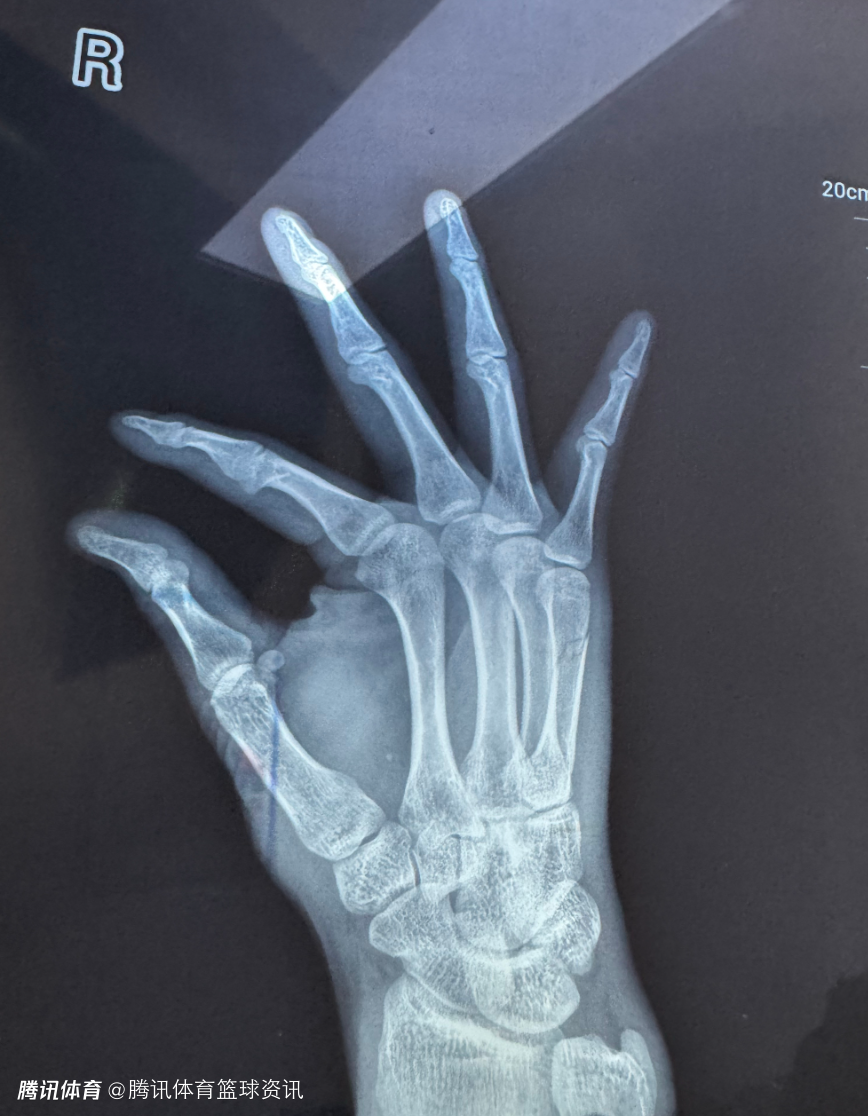

赛季报销!四川男篮官方:李玮颢右手第五掌骨骨折 预计伤停12周

2025-03-07 11:40北京时间3月7日,据四川男篮官方宣布,李玮颢在上场与吉林的比赛中遭遇手部受伤,被确诊为右手第五掌骨骨折,赛季报销。

我俱乐部球员李玮颢在2024-2025赛季CBA常规赛第三十六轮,3月5日四川丰谷酒业对阵吉林九台农商银行的比赛中,在一次防守对抗后右手感到不适,赛后前往医院就医;经专家诊断为右手第五掌骨骨折,预计伤停12周。

本赛季李玮颢被北控租借至四川,为球队出战的24场比赛,他在场均15.4分钟的上场时间里,得到5.1分2篮板,三项命中率分别为50%、34.8%和63.4%。